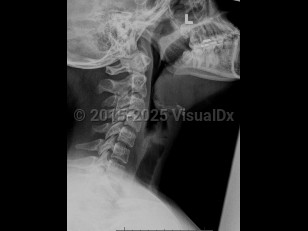

Epiglottitis is a potentially life-threatening inflammation of the epiglottis and supraglottic space caused by infection (eg, Haemophilus influenzae type b [Hib]) or injury (eg, foreign body, caustic substance, thermal damage). As the epiglottis swells, it can cause airway obstruction and create a medical emergency. Presenting symptoms include high fever, sore throat, difficulty swallowing, dyspnea, hoarseness, stridor, tachycardia, drooling, and hot potato voice or dysphonia.